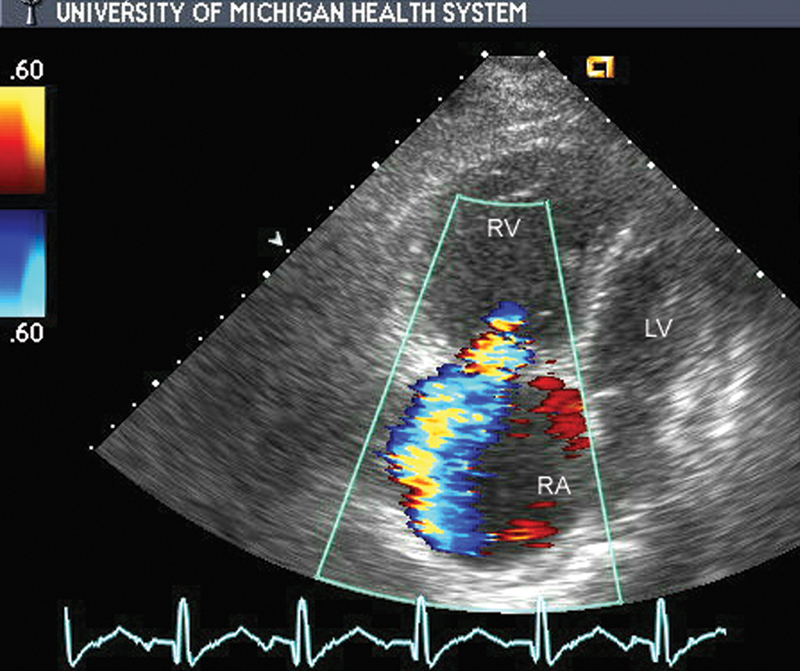

فحوصات تشخيصية لبعض امراض القلب والشرايين التاجية